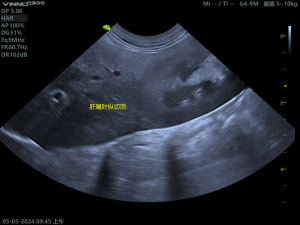

(1)正常肝脏影像

(2)胆囊粘液囊肿影像

胆囊内呈现“猕猴桃征”或“星芒状”的回声。胆囊壁增厚、胆泥淤积、可评估胆囊是否破裂。